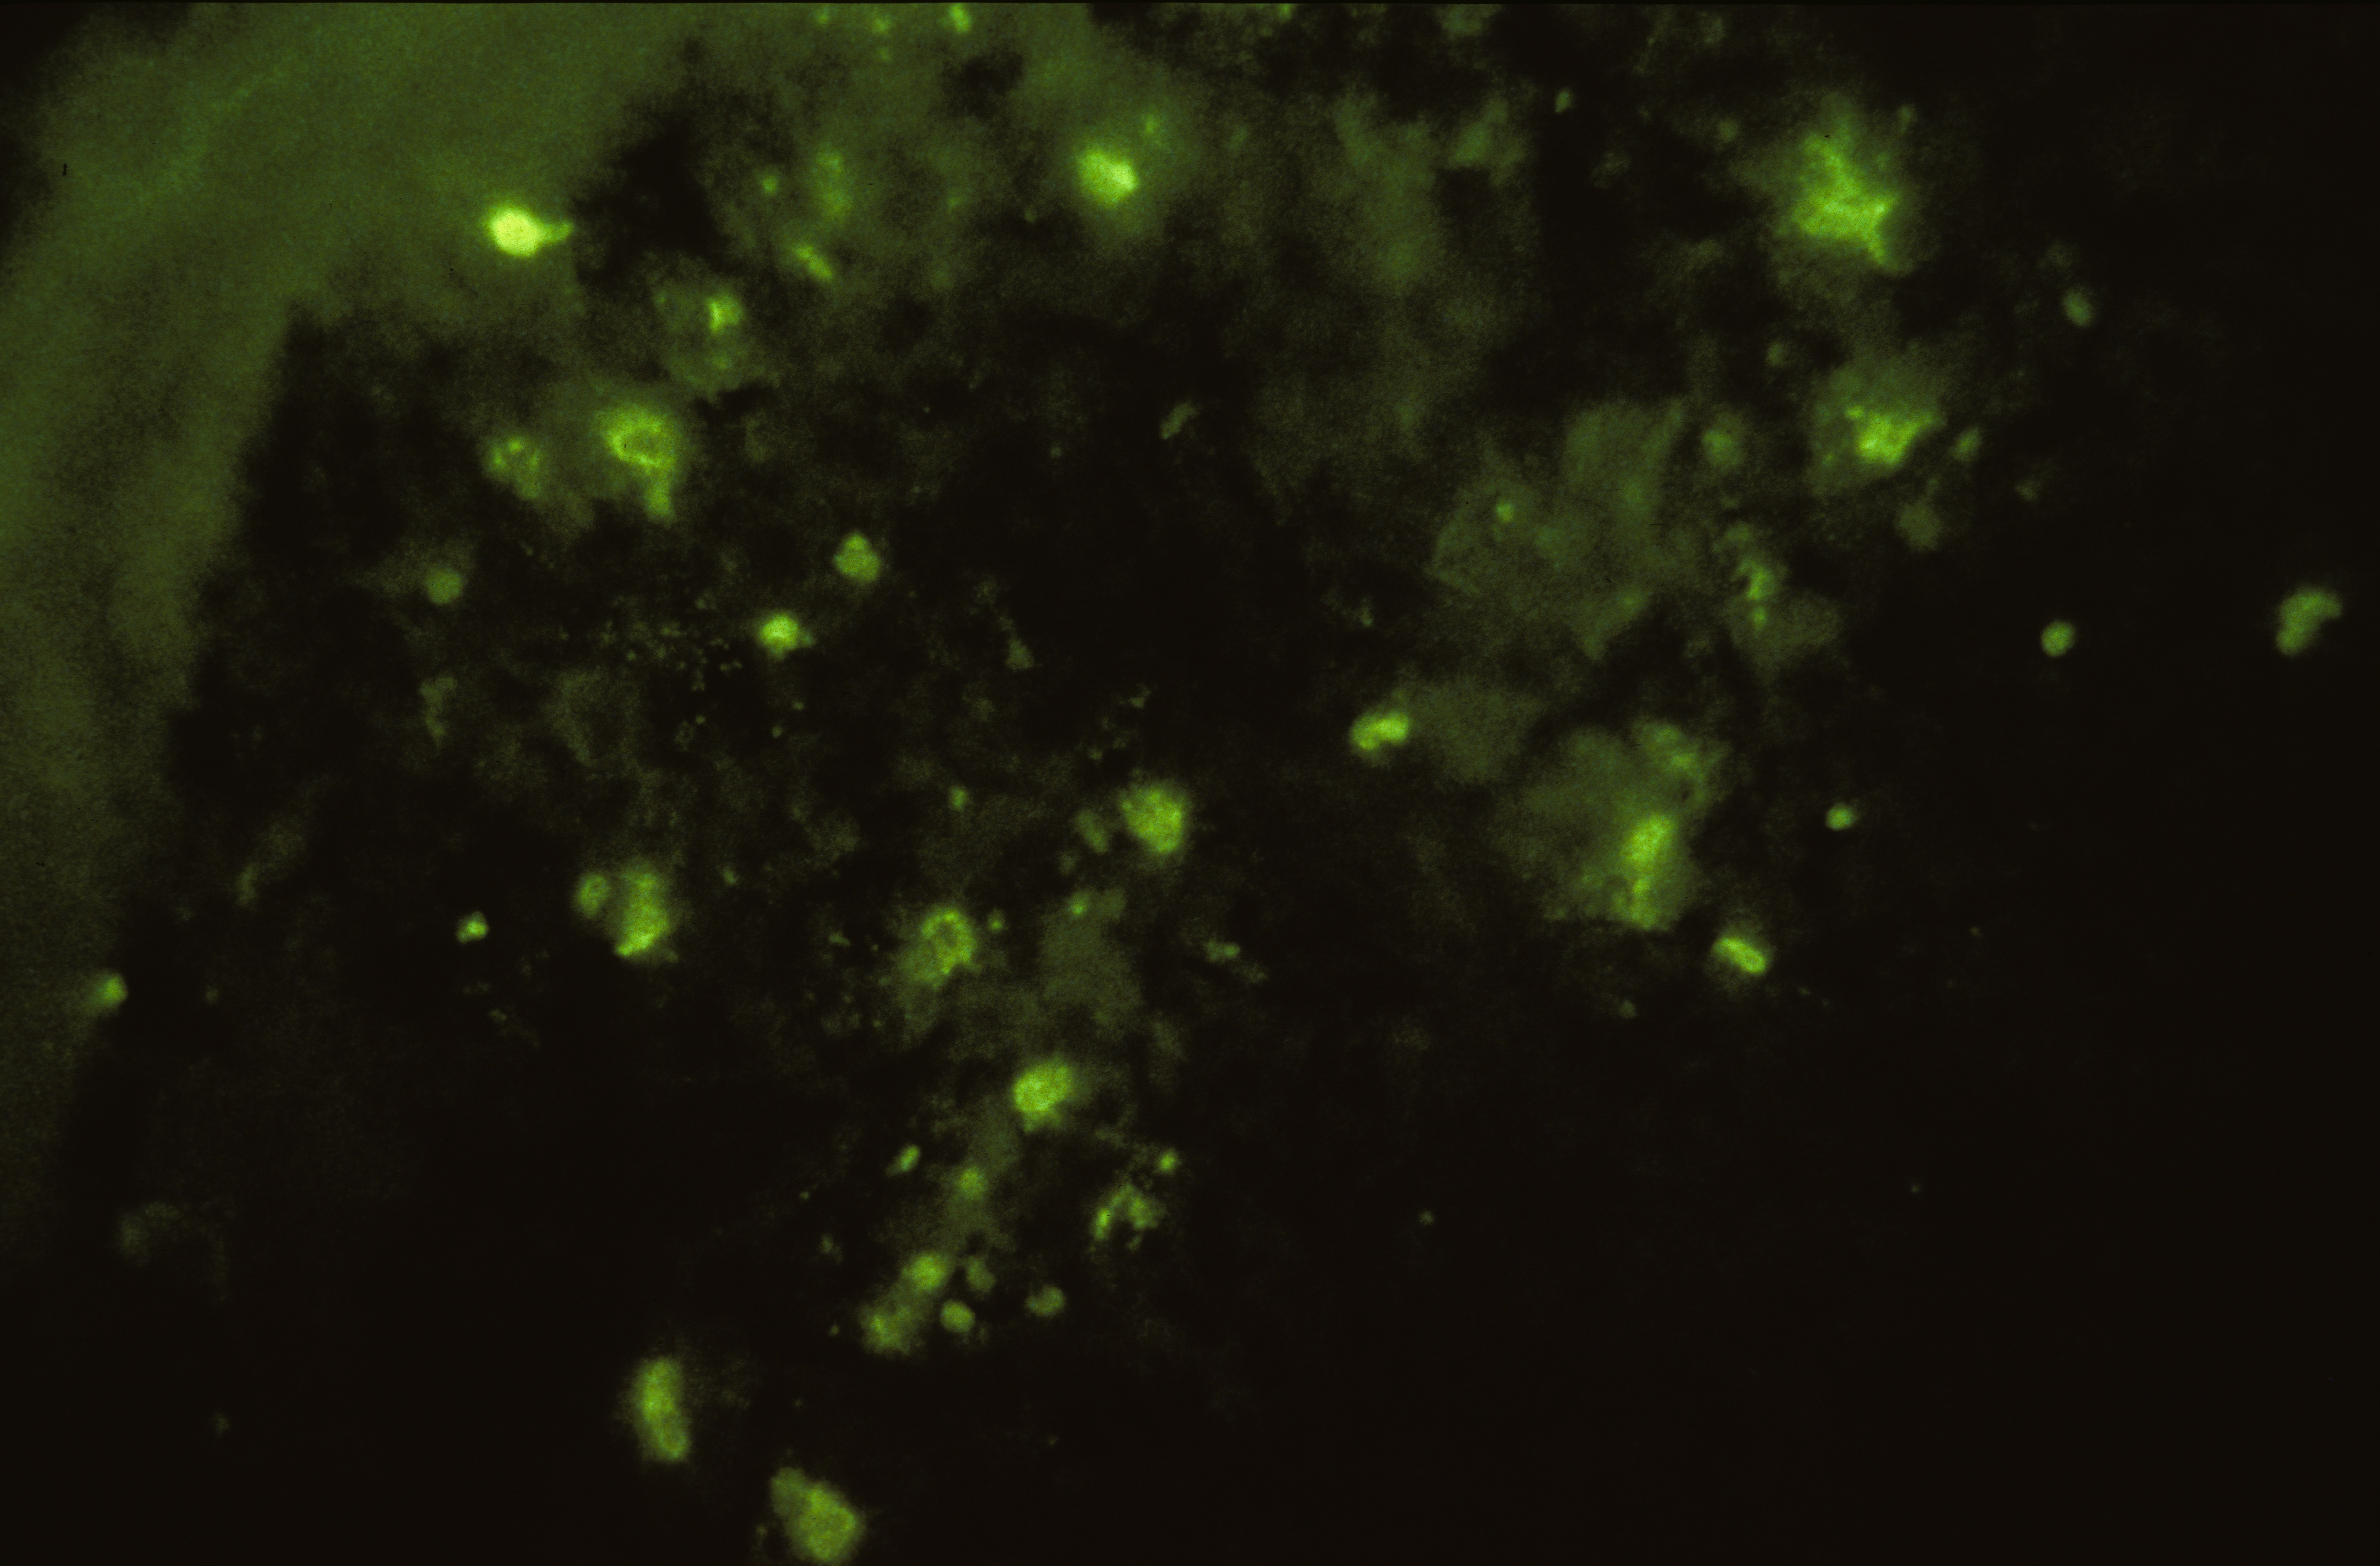

Marble spleen disease of ring-necked pheasants (slide study set no. 17) Item Info

Marble spleen disease of ring-necked pheasants (slide study set no. 17)

Slide study set #17, marble spleen disease of ring-necked pheasants, 2 sets (includes 40 color slides), undated